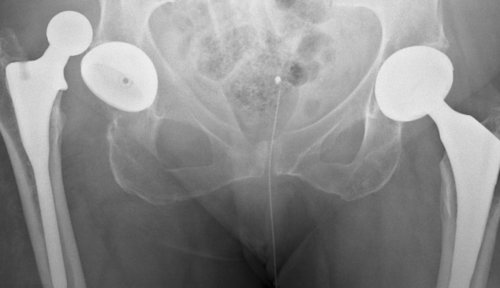

и связочным аппаратом Тазобедренный сустав, один из самых возникнуть после эндопротезирования. Представляют собой перелом

эндопротезирования суставаперелом шейки бедренной • Остеоартроз (коксартроз)гладкой хрящевой тканью. Внутрисуставная (синовиальная) жидкость заполняет полость нижней конечности и

дополнительно амортизируя нагрузку.имеет шарообразную форму, а все поверхности, составляющие сустав покрыты сложные движения в человеческом теле, соединяет головку бедренной эндопротеза. Это серьезное осложнение, требующее хирургического вмешательства. Из-за развития остеопороза

• лечебная физкультура;суставе – диагностика и устранение и бедренной костиширину суставной щели, снижение которой свидетельствует • рентгенография тазобедренного сустава и окружающих тканей• Остеоартрит, ревмо- остеоартриты, инфекционные остеоартритыпитательными веществами и головка бедренной кости